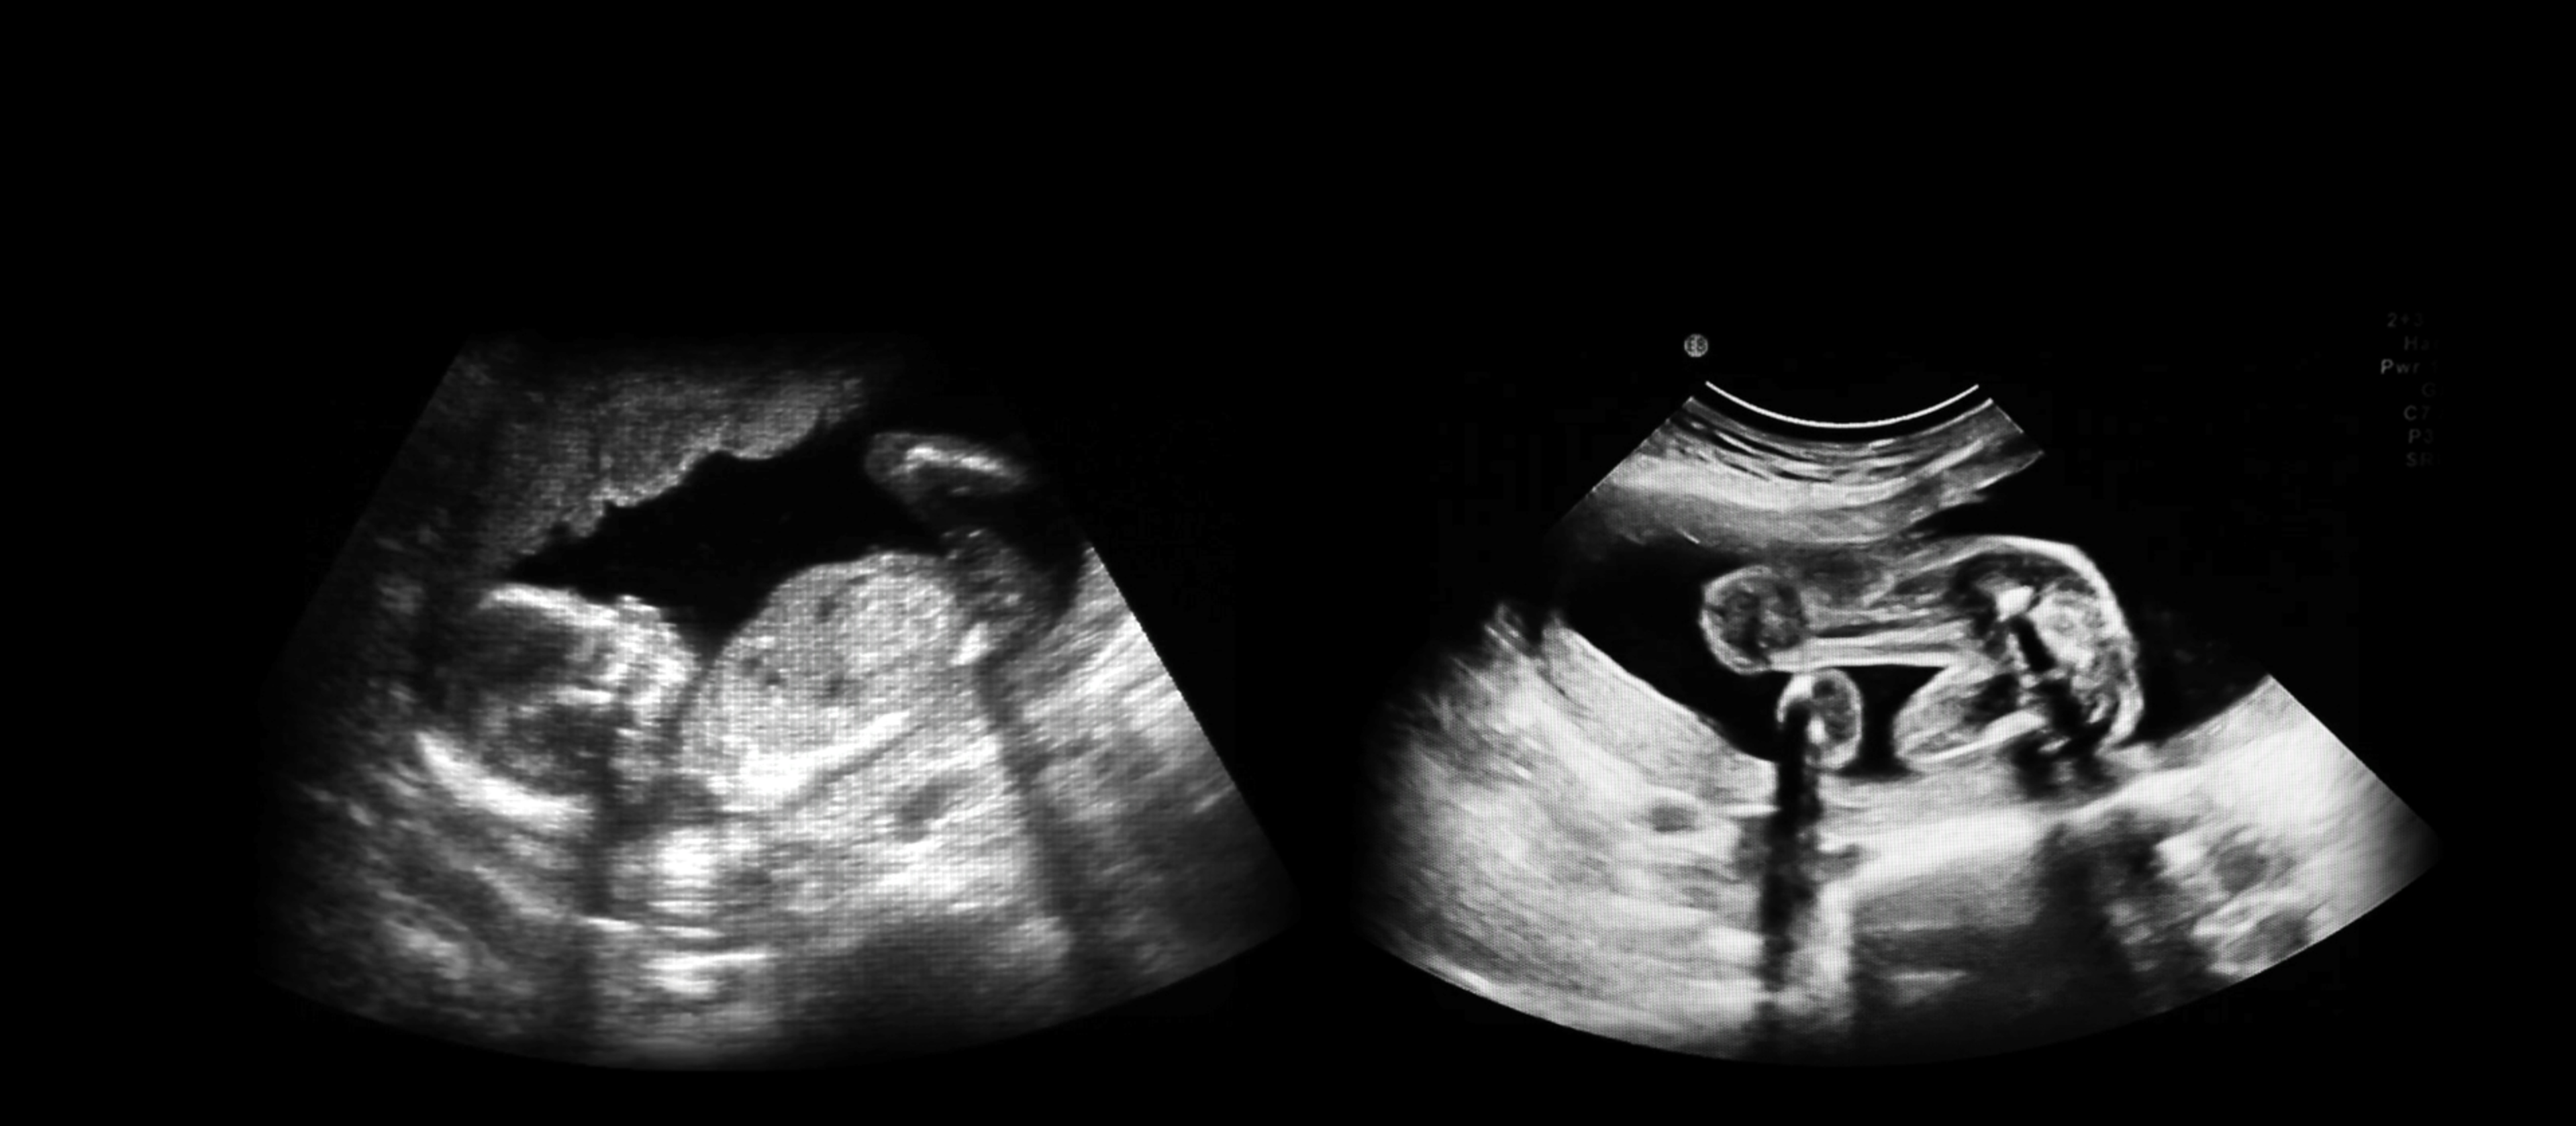

IN UTERO brings together for the first time convincing data that explains that we are not only our genes but a product of our environment as well.

Through enlightening and oftentimes poignant interviews with experts and pioneers, IN UTERO paints a complex tapestry of the human experience from conception to birth. Tapping into cultural myths, popular movies, and technological trends, the film demonstrates how our experiences in utero – particularly traumatic events – preoccupy us throughout our lives, impacting our decisions and shaping society.